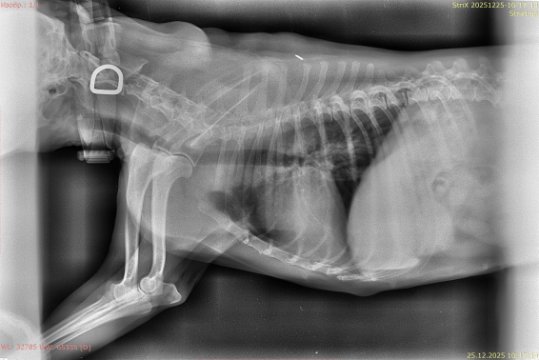

Рентген перед операцией и выписка после операции

Screenshot_2025-12-26-16-20-32-49_6431dcd7adc47d9b8b1ef172f656a796.jpg

IMG-20251226-WA0010.jpg